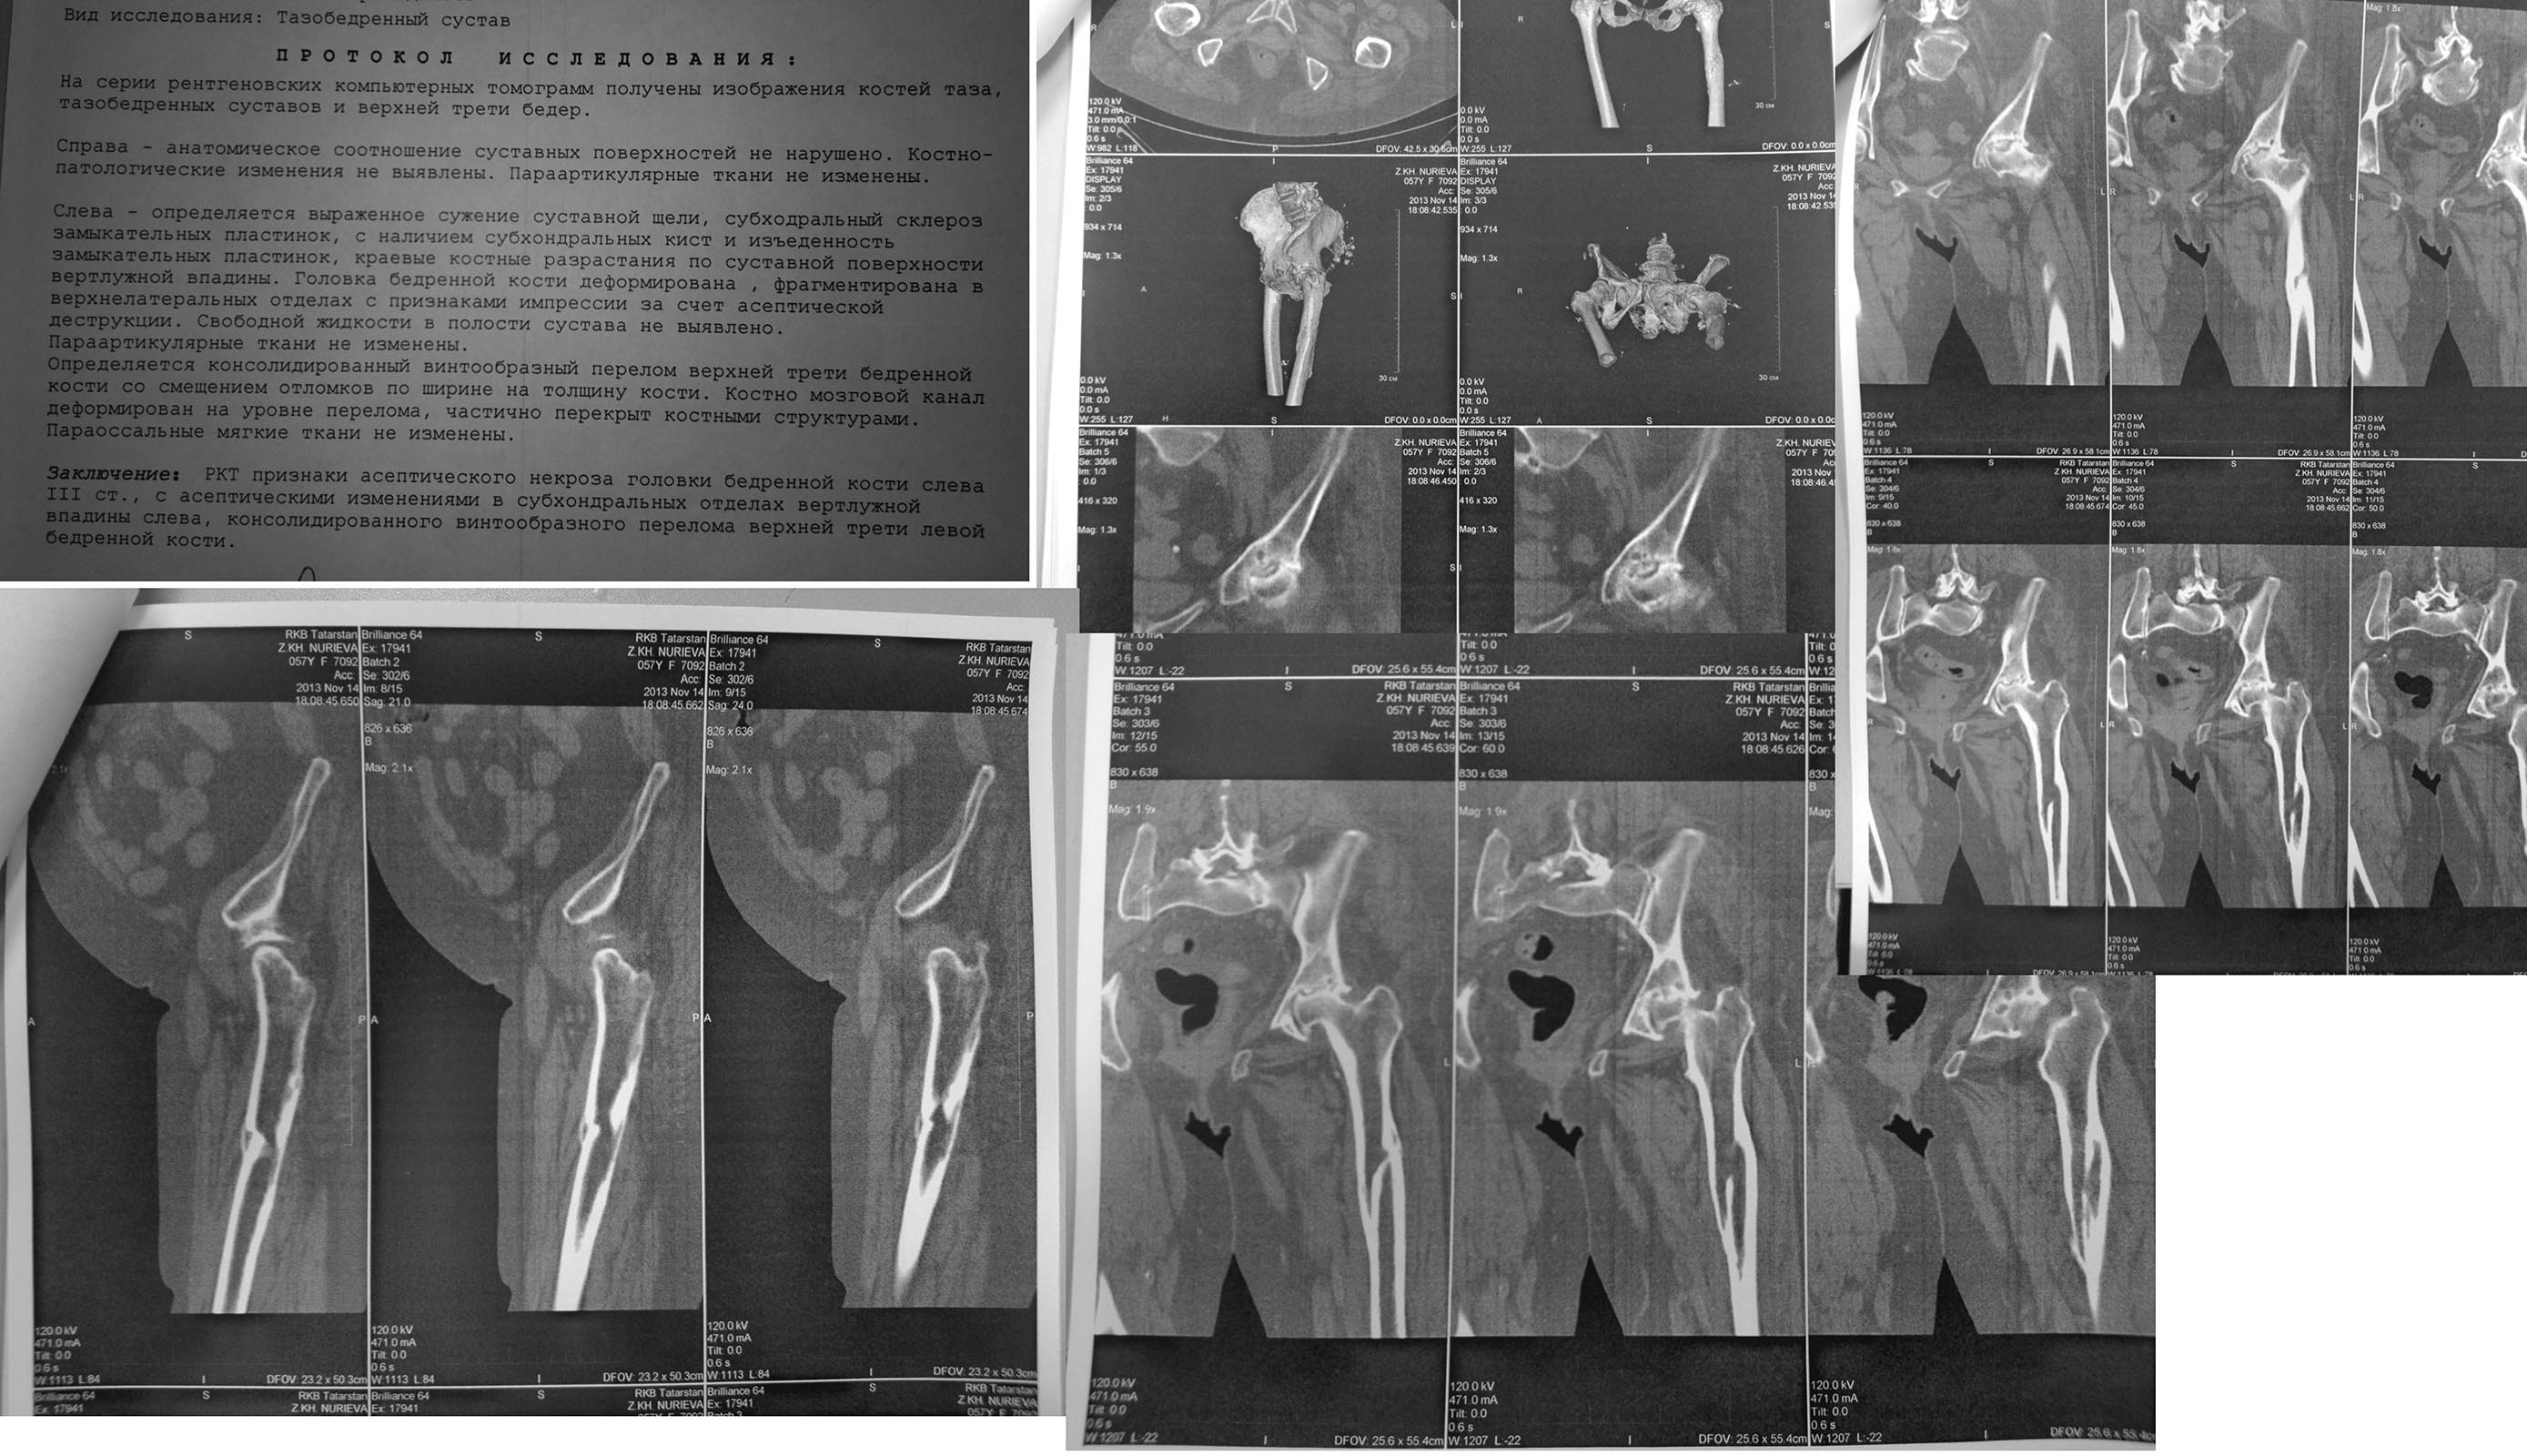

Добавляю результаты РКТ. Может мнение изменится?

По представленному снимку можно предположить вот такое планирование. Использована ножка М/L Taper Zimmer. Можно Другую аналогичную ножку. Попросите фирму Зиммер, пусть поменяют Вам одну ножку CLS (Spotorno) на ножку М/L Taper. По цене они одинаковы. А спишите как CLS (Spotorno), фирмы иногда идут на это, если сильно попросить. Это я говорю из своего опыта-иногда приходилось производить такой обмен.